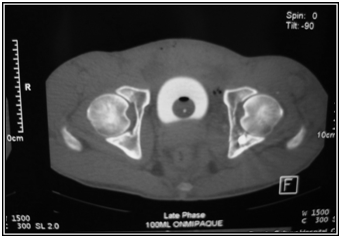

A 32 old male presented with a single gunshot wound to the right suprapubic area, with no exit. Radiographs revealed a bullet that appeared to be lodged in the left hip joint (Figures 1) A CT scan (Figures 2) and cystogram showed no associated injuries, with the bullet tract entering the quadrilateral surface of the left hip and the bullet buried in the posterior acetabular wall.

Figure 1 Radiographs at first presentation showing a bullet that appeared to be lodged in the left hip joint.

Figure 2 CT scan showed the bullet buried in the posterior acetabular wall.